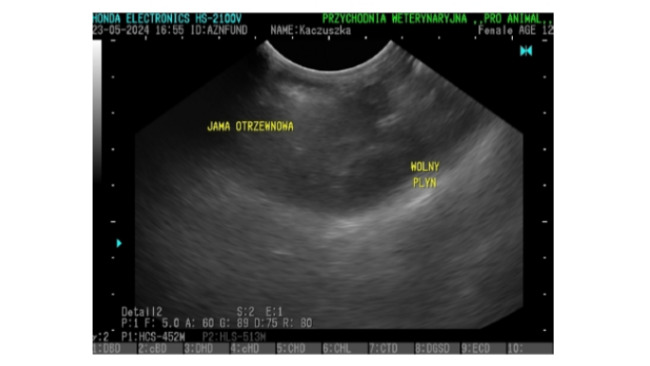

Seria badań, która wciąż trwa, sugeruje, że mamy do czynienia z kolejnym śmiertelnym wrogiem.

Dla Kaczuszki zapalenie otrzewnej to ogromna bitwa, którą bardzo trudno będzie wygrać.